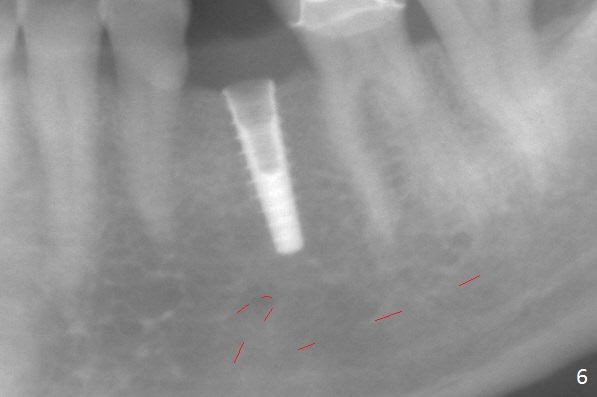

Initial osteotomy with 1.6 mm drill for 11 mm seems to be distal (Fig.1).  The trajectory should be changed as shown by the black line in Fig.2; the drawback would be close to the Mental Loop (red line).  Fortunately the trajectory is changed, but not so much as to be close the Loop when a 4x11 mm dummy implant is placed (Fig.3).   When a 4x13 mm IBS is placed with 46 Ncm, there is clearance from the Loop (Fig.4-6).  In fact there is no postop paresthesia.  The main point is no block anesthesia.  Infiltration anesthesia is administered with 34 mg Xylocaine with 17 mcg Epinephrine.  The patient experiences dull pain when the implant is placed (Fig.4-6).  After further anesthesia with 68 mg Septocaine, 17 mcg Epinephrine, the implant is torqued for a few turns (still with some discomfort).  Finally autogenous bone with Osteogen is placed around the implant following placement of a 4.5x4(2) mm abutment.  To reduce anxiety, a shorter implant should have been used. The patient complains of cold sensitivity in the lower left quadrant 4 months postop (Fig.7): the implant apparently close to the Mental Loop.  Without an immediate provisional, the gingiva around the abutment is healthy.